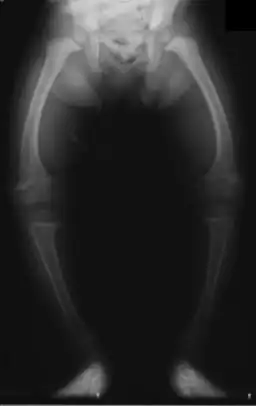

- Piernas arqueadas

- Las radiografías de los huesos pueden mostrar descalcificación o cambios en la forma o estructura de los huesos.